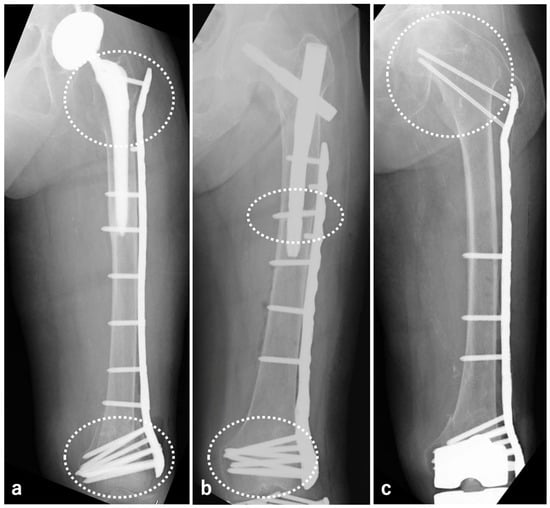

2.3.2. SFN

3. Results